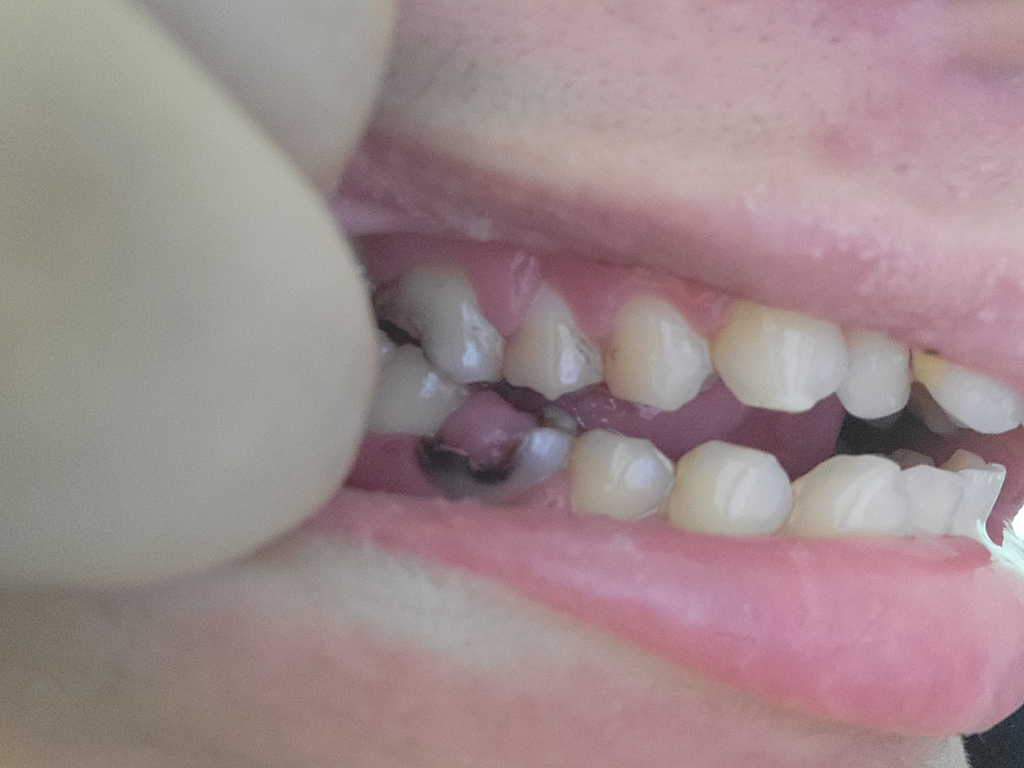

사진속에 이빨상태 차이가많이났아요

이빨 전사진보다 어떤가요 저는차이를잘물서그럼데

• 1번 째 사진

현재 충치가 매우 심할 것으로 보입니다. 이미 치수가 괴사된 경우라면 통증이 나타나지 않을 수 있으나 지금 상태에서는 예측하지 못한 통증이 나타날 수 있어 최대한 빨리 치과를 방문하는 것이 좋아 보입니다. 충치의 범위에 따라 신경치료나 크라운이 불가능하여 바로 발치를 해야할 수도 있어 보입니다. 치료 비용은 치료 방법에 따라 다르며 치과 방문 후 상담이 필요합니다.

아래쪽 치아는 상태가 많이 안좋아 보이네요. 아래쪽치아는 사진을 찍어봐야 알겟지만 발치가능성도 있어 보이며, 위쪽치아도 깨지신거 같은데 신경치료 가능성이 있으니 치과에 가셔서 빨리 치료를 받으세요.

해당부위는 충치가 크게 생긴것으로 보입니다.

신경치료를 동반한 보철 치료가 필요할수 있습니다.

치아가 많이 깨져있어 잇몸이 안 쪽으로 자라고 있는 아주 심각한 상황입니다.